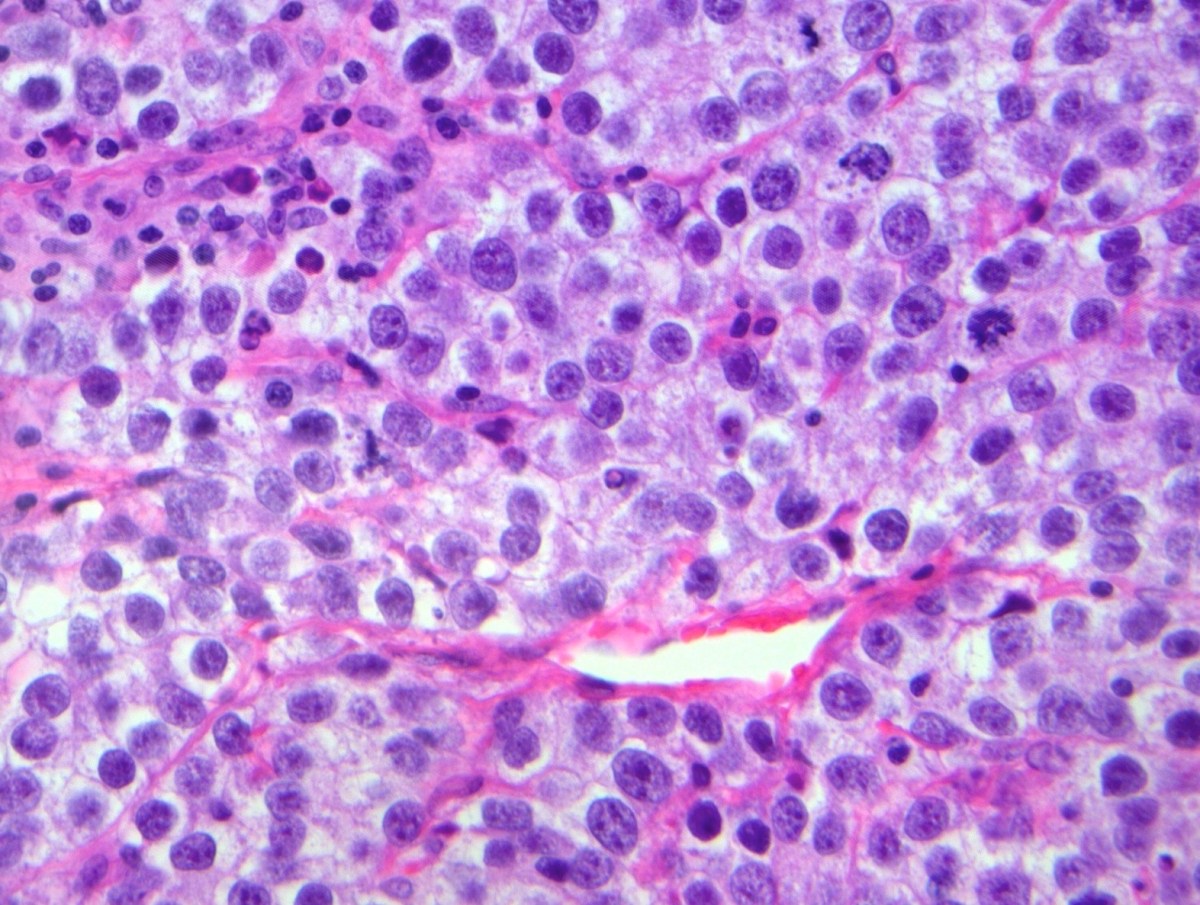

Disgerminoma — tuxumdonlarda paydo bo‘ladigan, kam uchraydigan, jinsiy hujayralardan kelib chiqadigan o‘sma turidir. Jinsiy hujayralar odatda ko‘payish jarayonida tuxum hujayralarga aylanadi. Shu hujayralarning nazoratsiz ko‘payishi saraton jarayoniga sabab bo‘lishi mumkin. Disgerminoma odatda bitta tuxumdonda rivojlanadi, tez o‘sishga moyildir, erta bosqichda aniqlansa davoga yaxshi javob beradi. Ko‘pincha yagona o‘sma o‘chog‘i sifatida kuzatiladi va yosh guruhda uchrashi bilan e’tiborni tortadi.

Sof disgerminoma. Eng ko‘p uchraydigan tur. Tuzilishi bir xilligi (gomogenligi) bilan ajralib turadi va ko‘pincha tuxumdon ichida chegaralangan bo‘ladi. Erta bosqichda aniqlanganda jarrohlik yo‘li bilan olib tashlanadi va natija odatda juda yaxshi bo‘ladi.